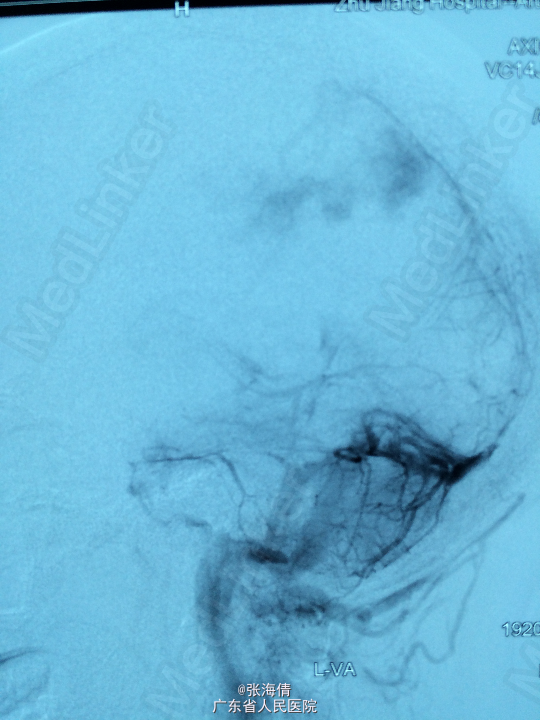

主诉:头晕、恶心6h 病史:患者男,22岁,2年来头晕、恶心症状多次出现,发作频率无明显规律,每次约2 min,无其他不适。6小时前上述症状加重,伴呕吐,呕吐物为胃内容物,外院CT平扫:示右侧颞顶叶见结节状稍高密度影,外院MR提示:平扫示右颞顶叶可见结节状稍长T1混杂T2信号影,大小约2.5 cm×2.1 cm×2.6 cm,边界较清晰,周围见长T1长T2水肿信号,SWI序列病变内未见明显低信号,DWI示信号稍高,增强扫描明显均匀强化,可见分叶,右侧脑室后角轻度受压

查体:全身未触及明显肿大淋巴结。脑膜刺激征:颈项强直,Kernig’S征阳性。 辅助检查:外院CT平扫:示右侧颞顶叶见结节状稍高密度影,外院MR提示:平扫示右颞顶叶可见结节状稍长T1混杂T2信号影,大小约2.5 cm×2.1 cm×2.6 cm,边界较清晰,周围见长T1长T2水肿信号,SWI序列病变内未见明显低信号,DWI示信号稍高,增强扫描明显均匀强化,可见分叶,右侧脑室后角轻度受压

诊断:脑膜瘤 处理:先予DSA以明确肿瘤供血情况,术中脑膜瘤供血丰富,用PVA颗粒超选到供血动脉将其闭塞。后再择期在气管全麻下行脑膜瘤切除术。

术后病理提示:脑膜瘤,WHO I级,瘤组织浸润脑组织。免疫组化:Ki一67(<1%)(+),CK(一),GFAP(一),Vimentin(+),EMA(+),P53(一),ER(一),PR(一)。 讨论:脑膜瘤首选方法为手术切除,手术切除脑膜瘤是最有效的治疗手段,但是由于其供血经常较为丰富,故可先行介入栓塞供血动脉后再行切除,这样可以降低手术风险和手术难度,改善患者手术预后。